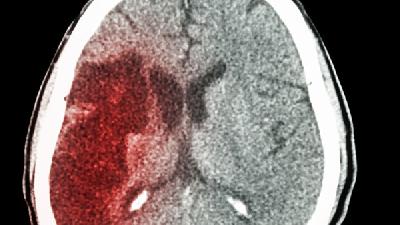

痉挛性脑瘫主要表现为肌张力增高、运动障碍、姿势异常及反射异常等症状,病情严重程度从轻度运动受限到完全丧失自主活动...

脑瘫可能由产前缺氧、早产低体重、新生儿黄疸、遗传代谢异常等原因引起,症状表现为运动障碍、肌张力异常等,需通过康复...

脑瘫的临床表现主要有运动发育迟缓、肌张力异常、姿势异常、伴随症状等,需根据具体类型综合评估。 1. 运动发育迟缓...

小儿脑瘫的症状表现主要包括运动发育迟缓、肌张力异常、姿势反射异常、语言障碍等,严重者可伴随智力障碍或癫痫发作。 ...